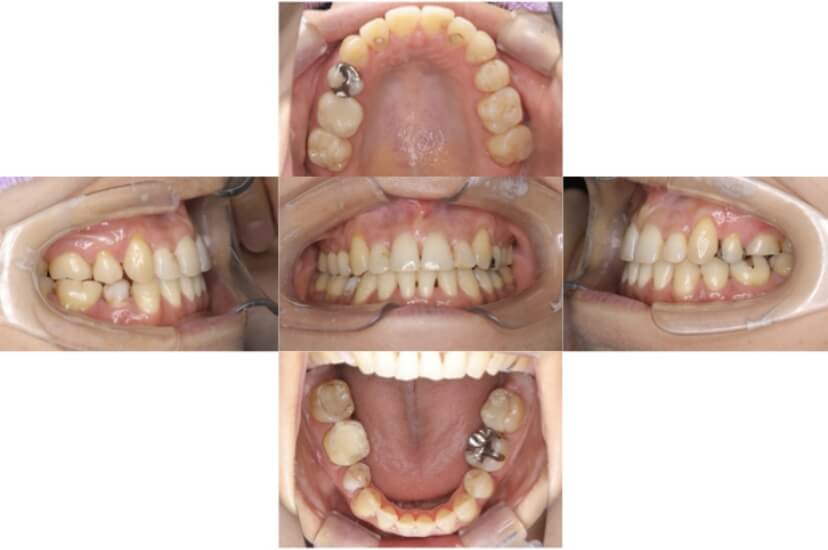

BEFORE

治療経過

上下顎叢生(上下の前歯のガタガタ)のケースです。

装置はラビアル(上下表側)で、上下顎の小臼歯を4本抜歯を行っています。抜歯したスペースを使って、上下の前歯の後方移動と叢生(ガタガタ)の改善を行っています。

主訴 歯並びが悪く、舌を噛んでしまうのを治したい。

年齢・性別 27歳 男性

お住まいの地域 東京都大田区

治療方針 抜歯スペースを利用して上下前歯の叢生(ガタガタ)の改善

抜歯部位 上下顎左右第一小臼歯

使用装置 ラビアル(上下表側)、顎間ゴム

治療期間 3年1か月

治療回数 30回